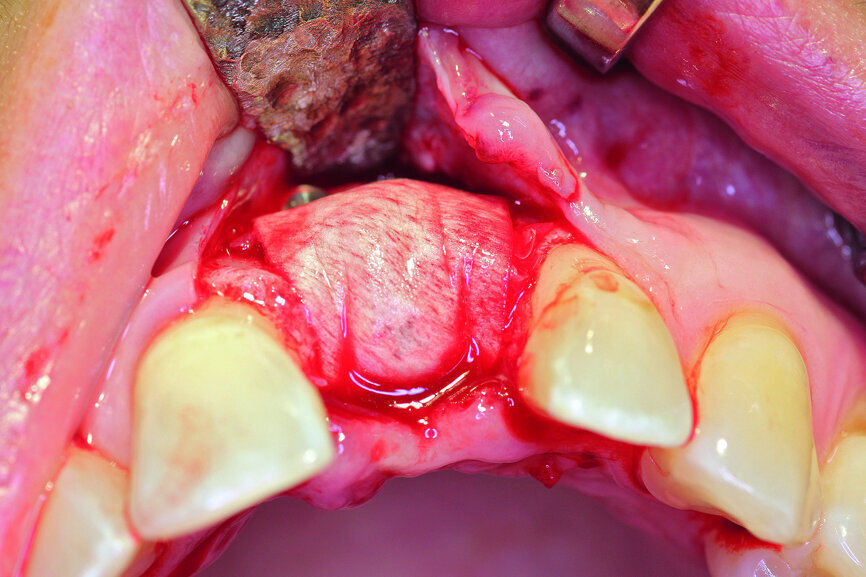

Fig. 3: After the extraction, the apical granulation tissue was excochleated.

After extraction of tooth #21, the apical granulation tissue was excochleated through a semilunar incision (Fig. 3). A two-stage procedure was performed to prevent failure of osseointegration of the ceramic implant and to preserve the soft-tissue structures (papillae and attached gingiva). A claspless prosthesis made from Valplast (Valplast International) served as a temporary restoration. The implant site in region #21 was uncovered after five months (Fig. 4). A two-piece ceramic implant (diameter: 4.2 mm; length: 12.0 mm) was then inserted (Figs. 5a & b). The guidelines for implant placement in the aesthetic zone and the drilling procedure specified by the manufacturer were observed.13, 14 Both vertical and transverse insertion depth are decisive for prosthetic success. The implant can be placed between 1.6 mm and 0.6 mm supracrestally because of a special thermal etching procedure in the collar region; the insertion depth is determined by the gingival height and the existing bone of the adjacent teeth. The implant positioning should be approximately 2–3 mm subgingivally because the abutments are added 1 mm above implant shoulder level. Transversal bone augmentation was performed with a mixture of autogenous bone chips (retrieved from the retromolar mandible), xenograft (Geistlich Bio-Oss, Geistlich Biomaterials) and guided bone regeneration (Jason membrane, botiss biomaterials; Figs. 6a & b). The exposure was performed after four months using a PEEK gingiva former (Fig. 7).